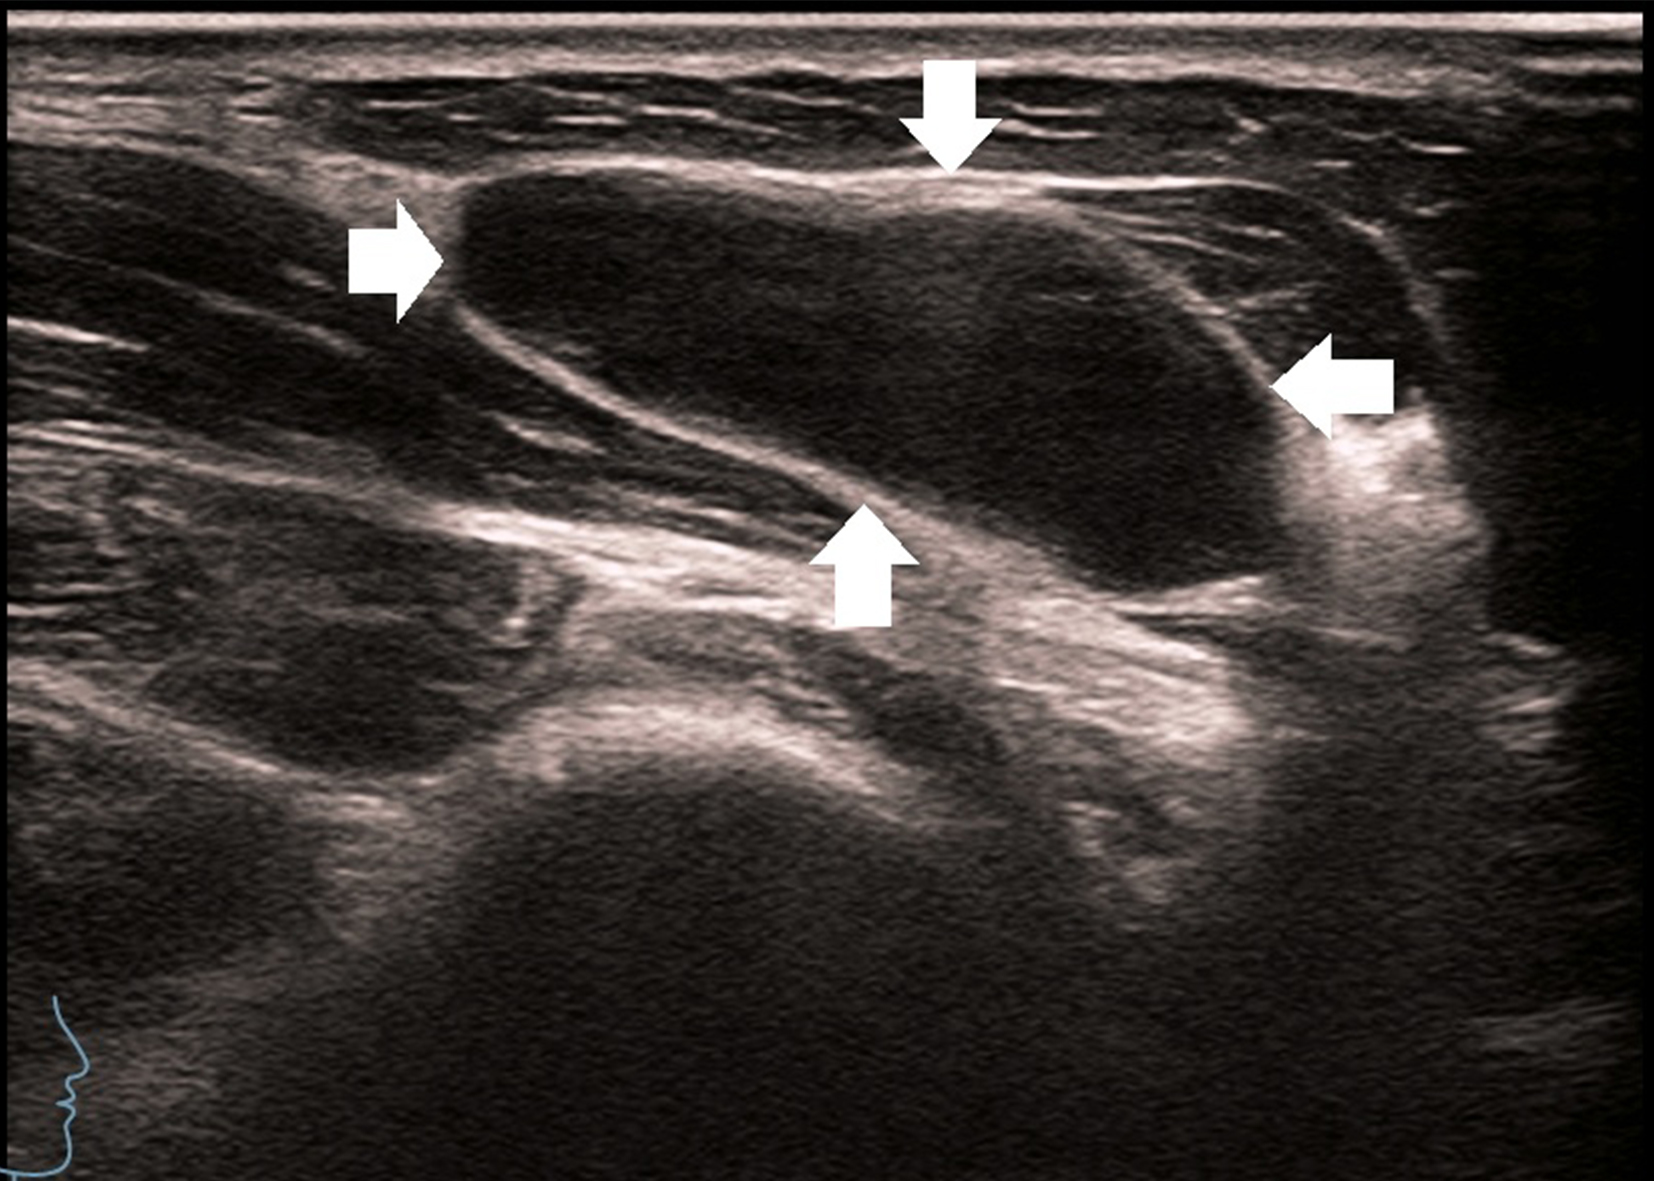

Figure 3

A 27-year-old man with enlarged lymph nodes in his right neck. Ultrasound showed significant enlargement of the lymph nodes, thickening of the cortex, disappearance of the lymphatic portal, and enlarged lymph nodes, as shown by the arrow.